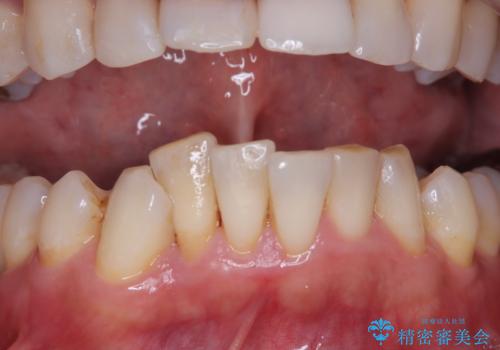

- 矯正治療前にステインを取りたいとのことで来院されました。ステインは前歯のみだったため、PMTC30分コースを行いました。

PMTCとは、歯科の専門家が器械を使用して行う歯のクリーニングのことです。普段の歯磨きでは取り切れない溝、キワなどの細かい部分も徹底的に除去します。ステインや歯石などが付着したままだと、虫歯や歯周病の発見がしずらいことがあります。特に矯正治療前には、念入りな虫歯や歯周病チェックが必要なため、PMTCでしっかりと汚れを除去しておくことが大切です。